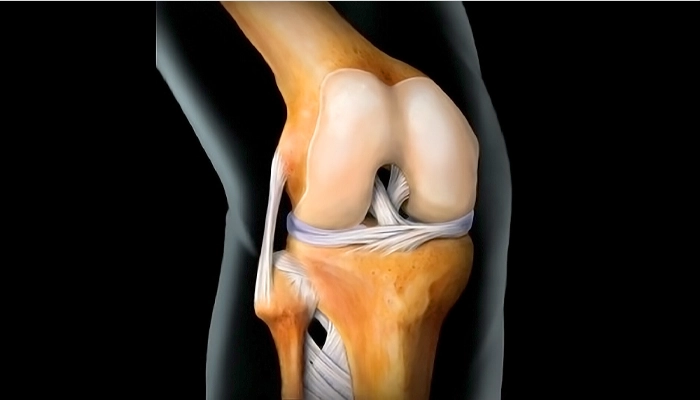

به گزارش خبرگزاری صدا و سیما، مرکز البرز، طاهرخانی با اشاره به ارتقای خدمات درمانی گفت: از سال گذشته تاکنون، نزدیک به ۹۰۰ عمل تعویض مفصل زانو به صورت کاملاً رایگان انجام شده است که هزینه هر عمل در مراکز خصوصی میتواند تا ۲۰۰ میلیون تومان برسد، اما این خدمات بدون هیچ هزینهای و رایگان ارائه می شود.